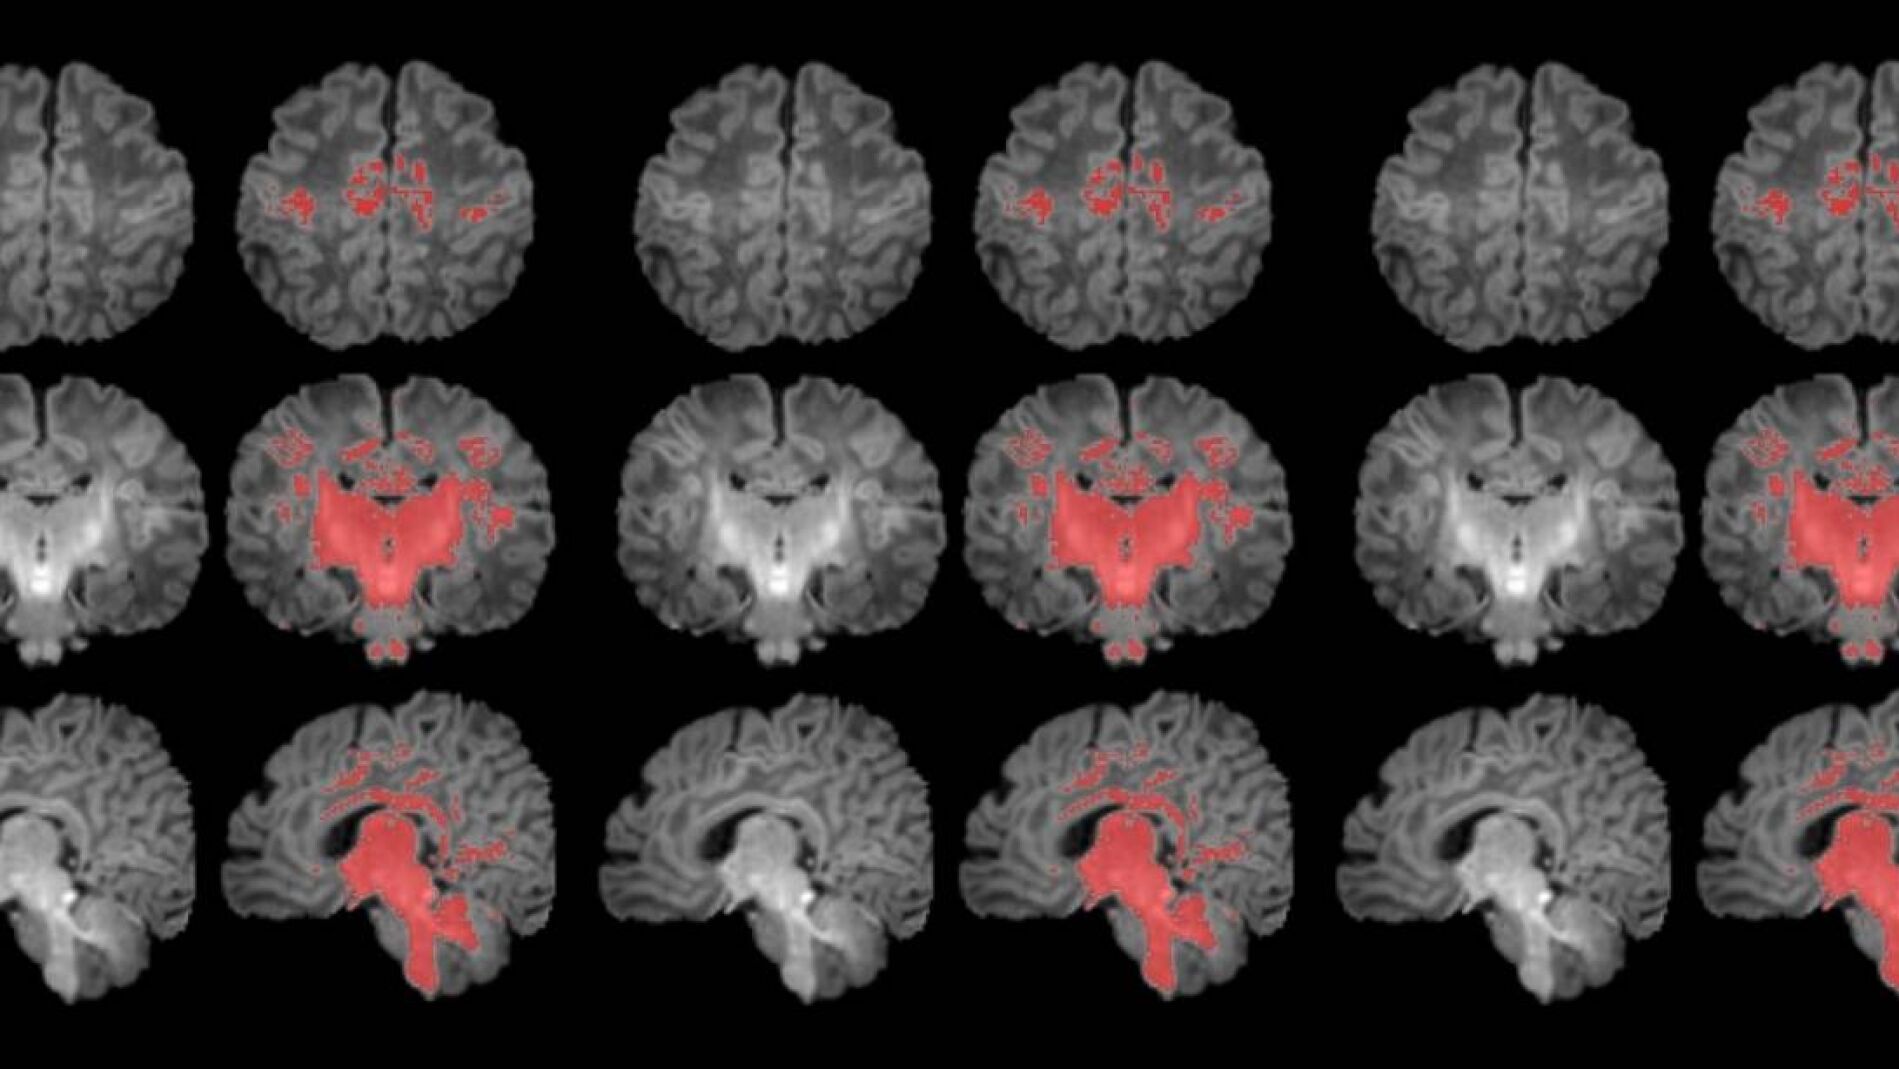

Para llevar a cabo el estudio se reclutó a mujeres embarazadas en seguimiento en el Hospital Clínic Barcelona, el Hospital de Sant Pau y el Hospital Sant Joan de Déu. Se monitorizaron los niveles de contaminantes atmosféricos a los cuales estaban expuestos durante la gestación y, después del parto, se seleccionó a 132 recién nacidos. A estos se les realizó una resonancia magnética antes de cumplir el primer mes de vida para observar el grado de maduración cerebral según sus niveles de mielinización.

Los resultados muestran una correlación clara entre una mayor exposición materna a PM2.5 durante el embarazo y una menor mielinización en el cerebro de los recién nacidos.

La mielinización es un proceso clave en la maduración del cerebro, en que la mielina recubre las conexiones neuronales y las hace eficientes para la transmisión de información. Los recién nacidos de madres expuestas a niveles más altos de partículas finas en suspensión durante el embarazo muestran una mielinización más lenta en esta etapa tan precoz de la vida.